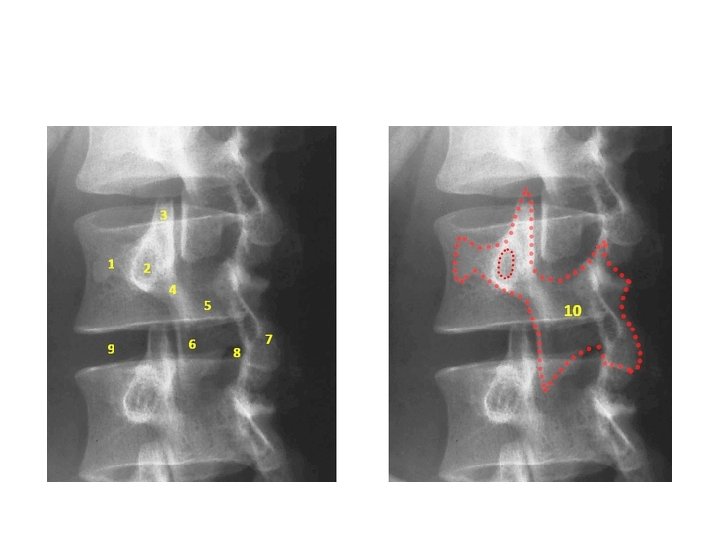

• Imaging studies : - X-ray : AP radiographic findings are usually normal in spondylolysis. The oblique views ( Rt. And Lt ) are particularly screened for the "Scotty dog" lesion in the pars interarticularis. The pars defect is represented by the collar on the Scotty dog. - ( 99 m Tc) / SPECT bone scan : superior to CT/MRI : these scans can aid in establishing the acuity of the lesion or in identifying the site of the problem in an athlete with negative plain radiography results but whose clinical course is suggestive of a pars interarticularis fracture.

• Imaging : - X-ray : AP , lateral , oblique * on lateral view : forward slip is evident. * on oblique view : gap in pars interarticularis. - MRI : to evaluate impingement of neural elements. - CT : for bony pathology. - CT myelogram : when MRI contraindicated.